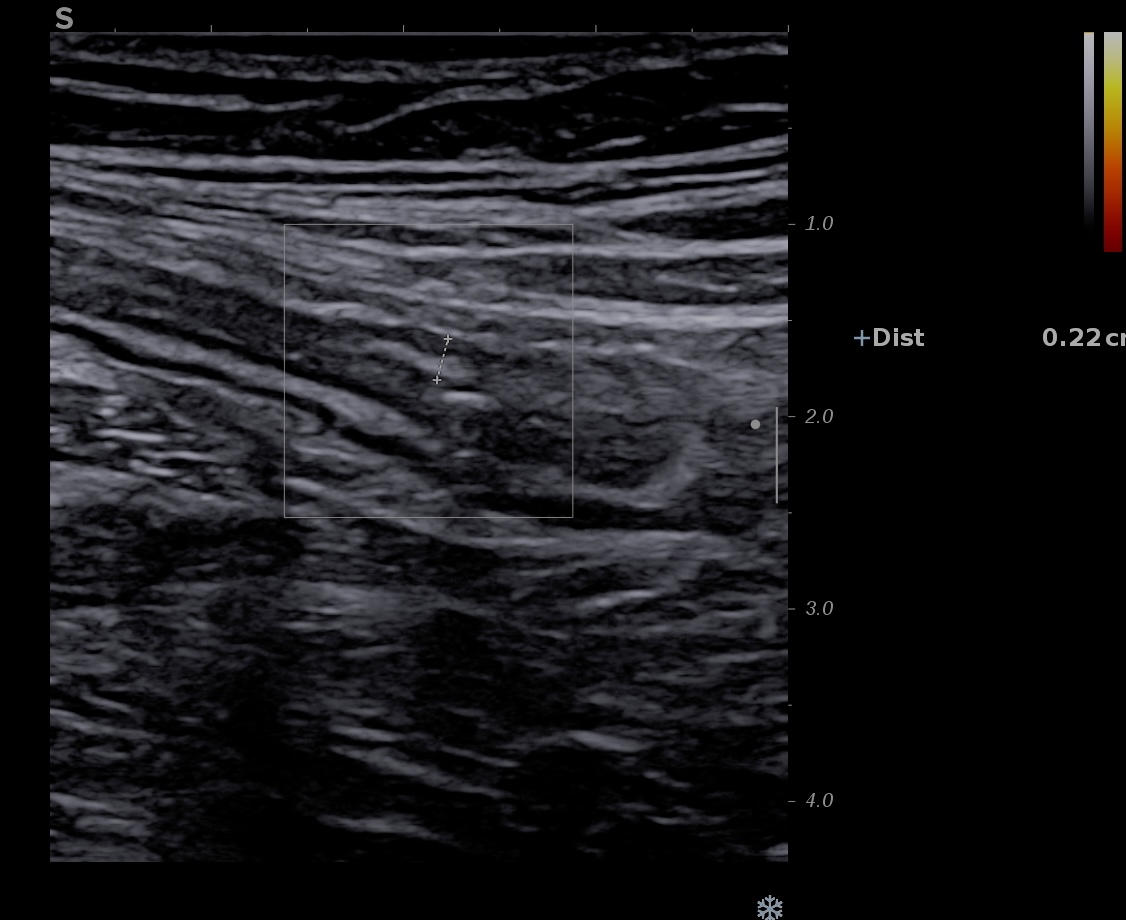

Aucune activité Doppler

Paroi non épaissie, aucune actibvité Doppler dans la fenêtre

- Limberg 0 Aucun signal Doppler (paroi intestinale normale, pas de vascularisation détectable)